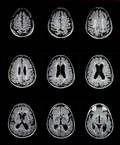

МРТ является магнитно-резонансная томография, специальный тест визуализации, которая не использует рентгеновских лучей. Эта процедура дает очень подробные изображения мозга, структуры лица, и пазух. В целом, МРТ лучше, чем КТ при определении острых приступов, инфекции и рак. Внутривенно краситель называется гадолиний иногда используется для получения лучшего изображения.